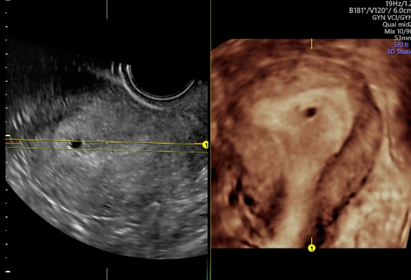

子宫容积成像

也就是4D超声波技术,是目前世界上最先进的彩色超声技术。四维成像技术(4D),能直观、立体显示人体器官的三维结构及动态、实时地观察立体结构,而以往的二维成像技术只能显示人体器官的某一切面。